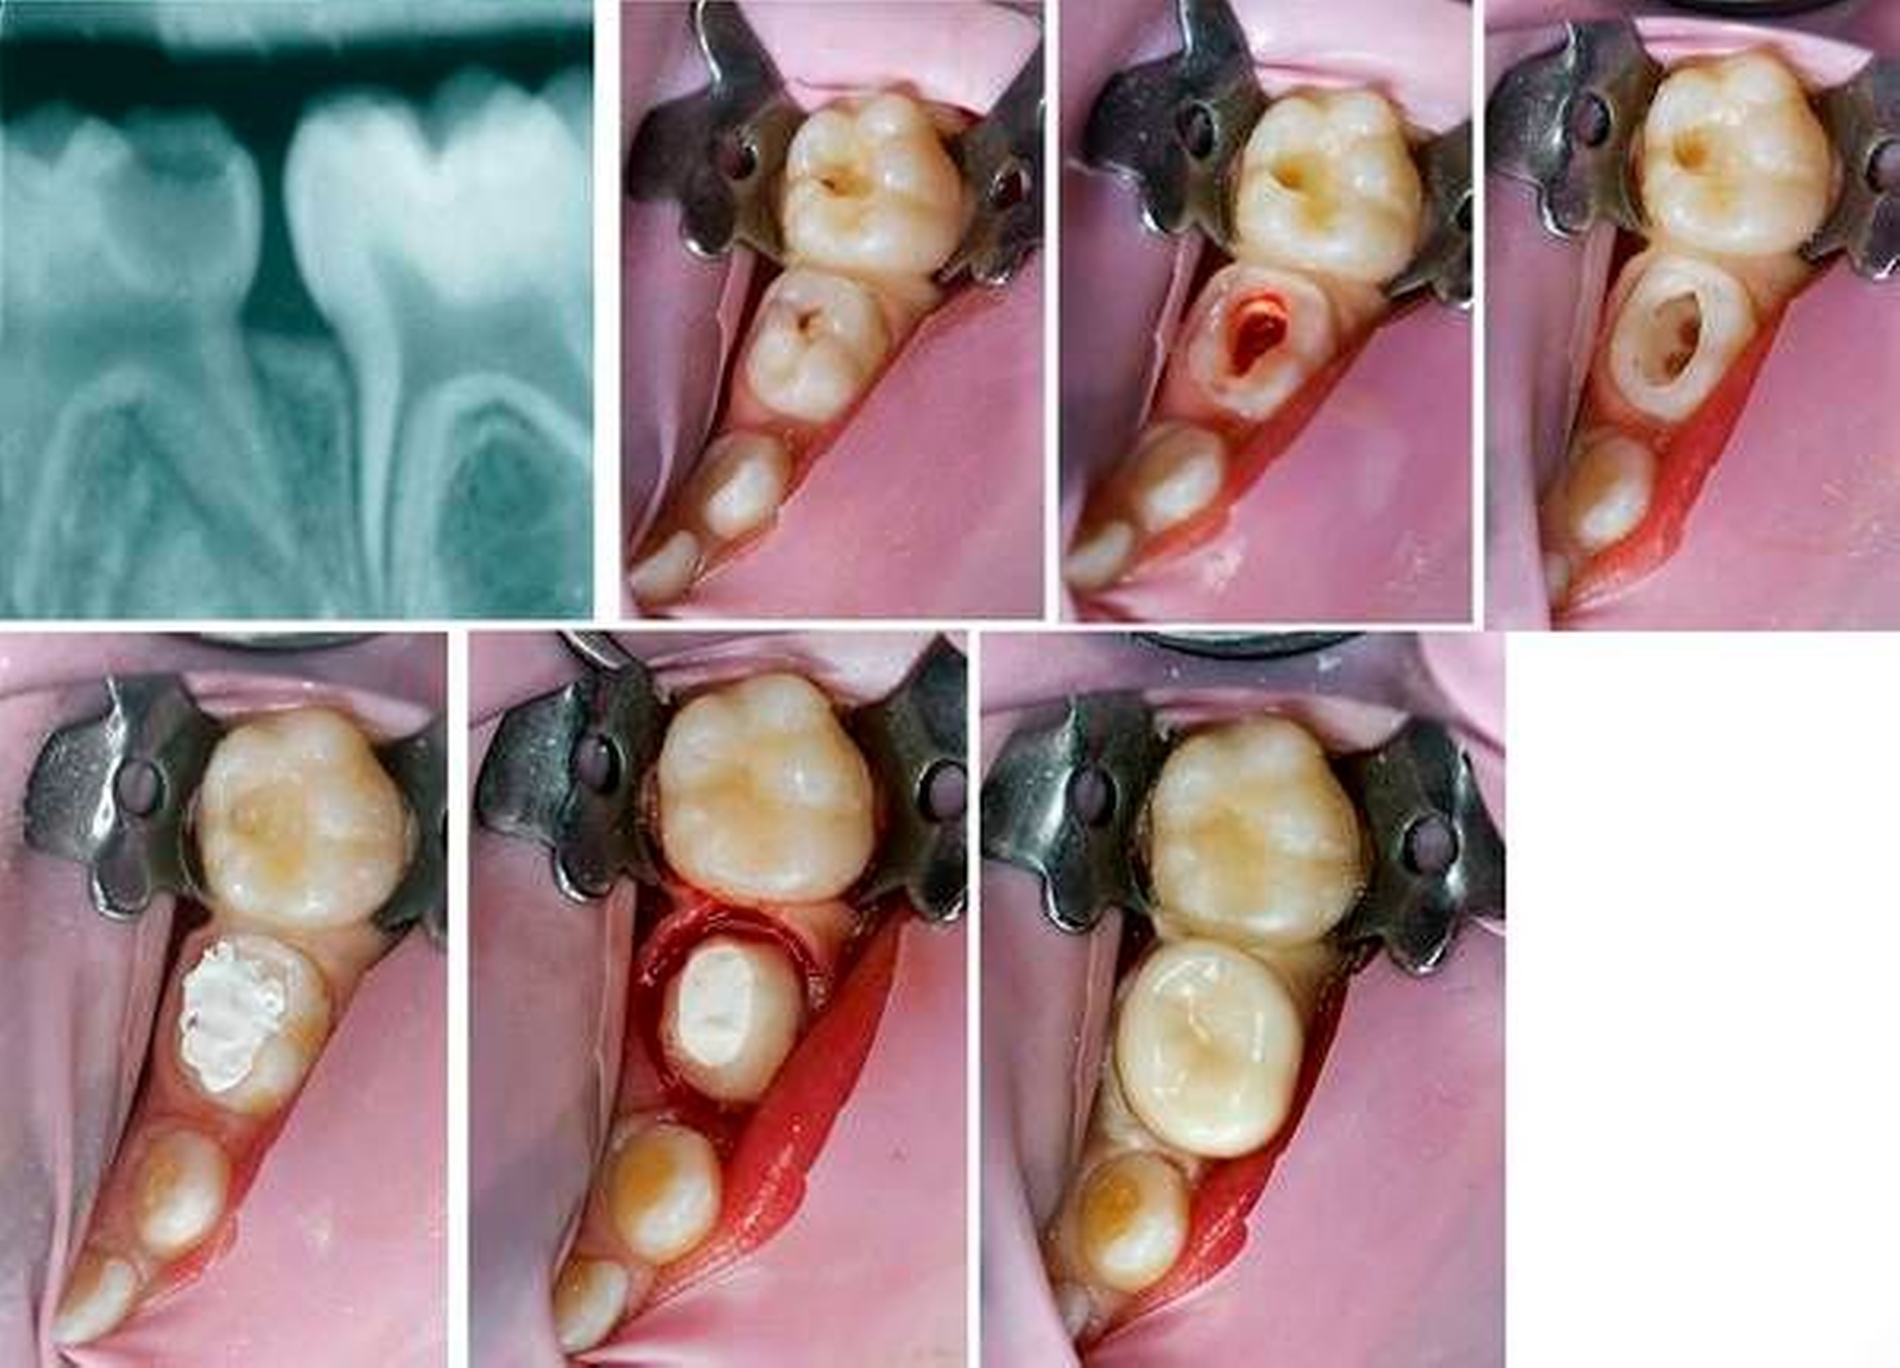

Die Vitalamputation am Milchmolaren sollte zum Standardrepertoire der allgemeinzahnärztlichen Praxis gehören. Die einzelnen Schritte werden im Folgenden erklärt und in den Abbildungen 7a bis 7g dargestellt. Der Eingriff erfolgt in lokaler Anästhesie (Oberflächenanästhesie und Infiltration im Oberkiefer sowie Leitungsanästhesie im Unterkiefer). Nach jeder endodontischen Maßnahme ist eine Überkronung des jeweiligen Zahnes aus Gründen der Stabilität und des bakteriendichten Verschlusses erforderlich. Daher kann direkt nach der endodontischen Behandlung die Präparation für die Krone erfolgen. Das Pulpadach wird trepaniert und die Kronenpulpa bis an die Kanaleingänge hochtourig mit einem Diamanten oder Rosenbohrer unter Wasserkühlung entfernt. Jetzt kann noch einmal der Zustand der Pulpa beurteilt werden.

Eine hellrote, gut kontrollierbare Blutung spricht für einen symptomlosen Zahn, dessen Entzündung auf die Kronenpulpa begrenzt ist. Eine hyperämische, dunkelrote Blutung lässt auf eine Entzündung der Wurzelpulpa schließen und gilt als Kontraindikation für die Vitalamputation [Fuks, 2005]. Nach Säuberung und Trocknung der Kavität mittels Multifunktionsspritze wird ein mit Eisen(III)sulfat getränktes Wattepellet für 20 bis 30 Sekunden auf den Pulpastumpf gedrückt, um die Blutung zu stillen und ein Koagulum zu vermeiden [Fuks, 2008]. Der anschließende Wundverband sollte sowohl bakterizid als auch gewebefreundlich sein. Gute Ergebnisse liefert dabei beispielsweise IRM (Dentsply Sirona, Deutschland), ein Zinkoxid-Eugenol-Zement, der gegen den Pulpenkammerboden und die Kanaleingänge kondensiert wird [Seale und Coll, 2010]. Eine teurere Variante mit ebenfalls sehr guten Erfolgsaussichten stellt die Vitalamputation mit einem MTA-Zement dar. Dabei findet die Blutstillung mit Kochsalz statt [Simancas et al., 2010].